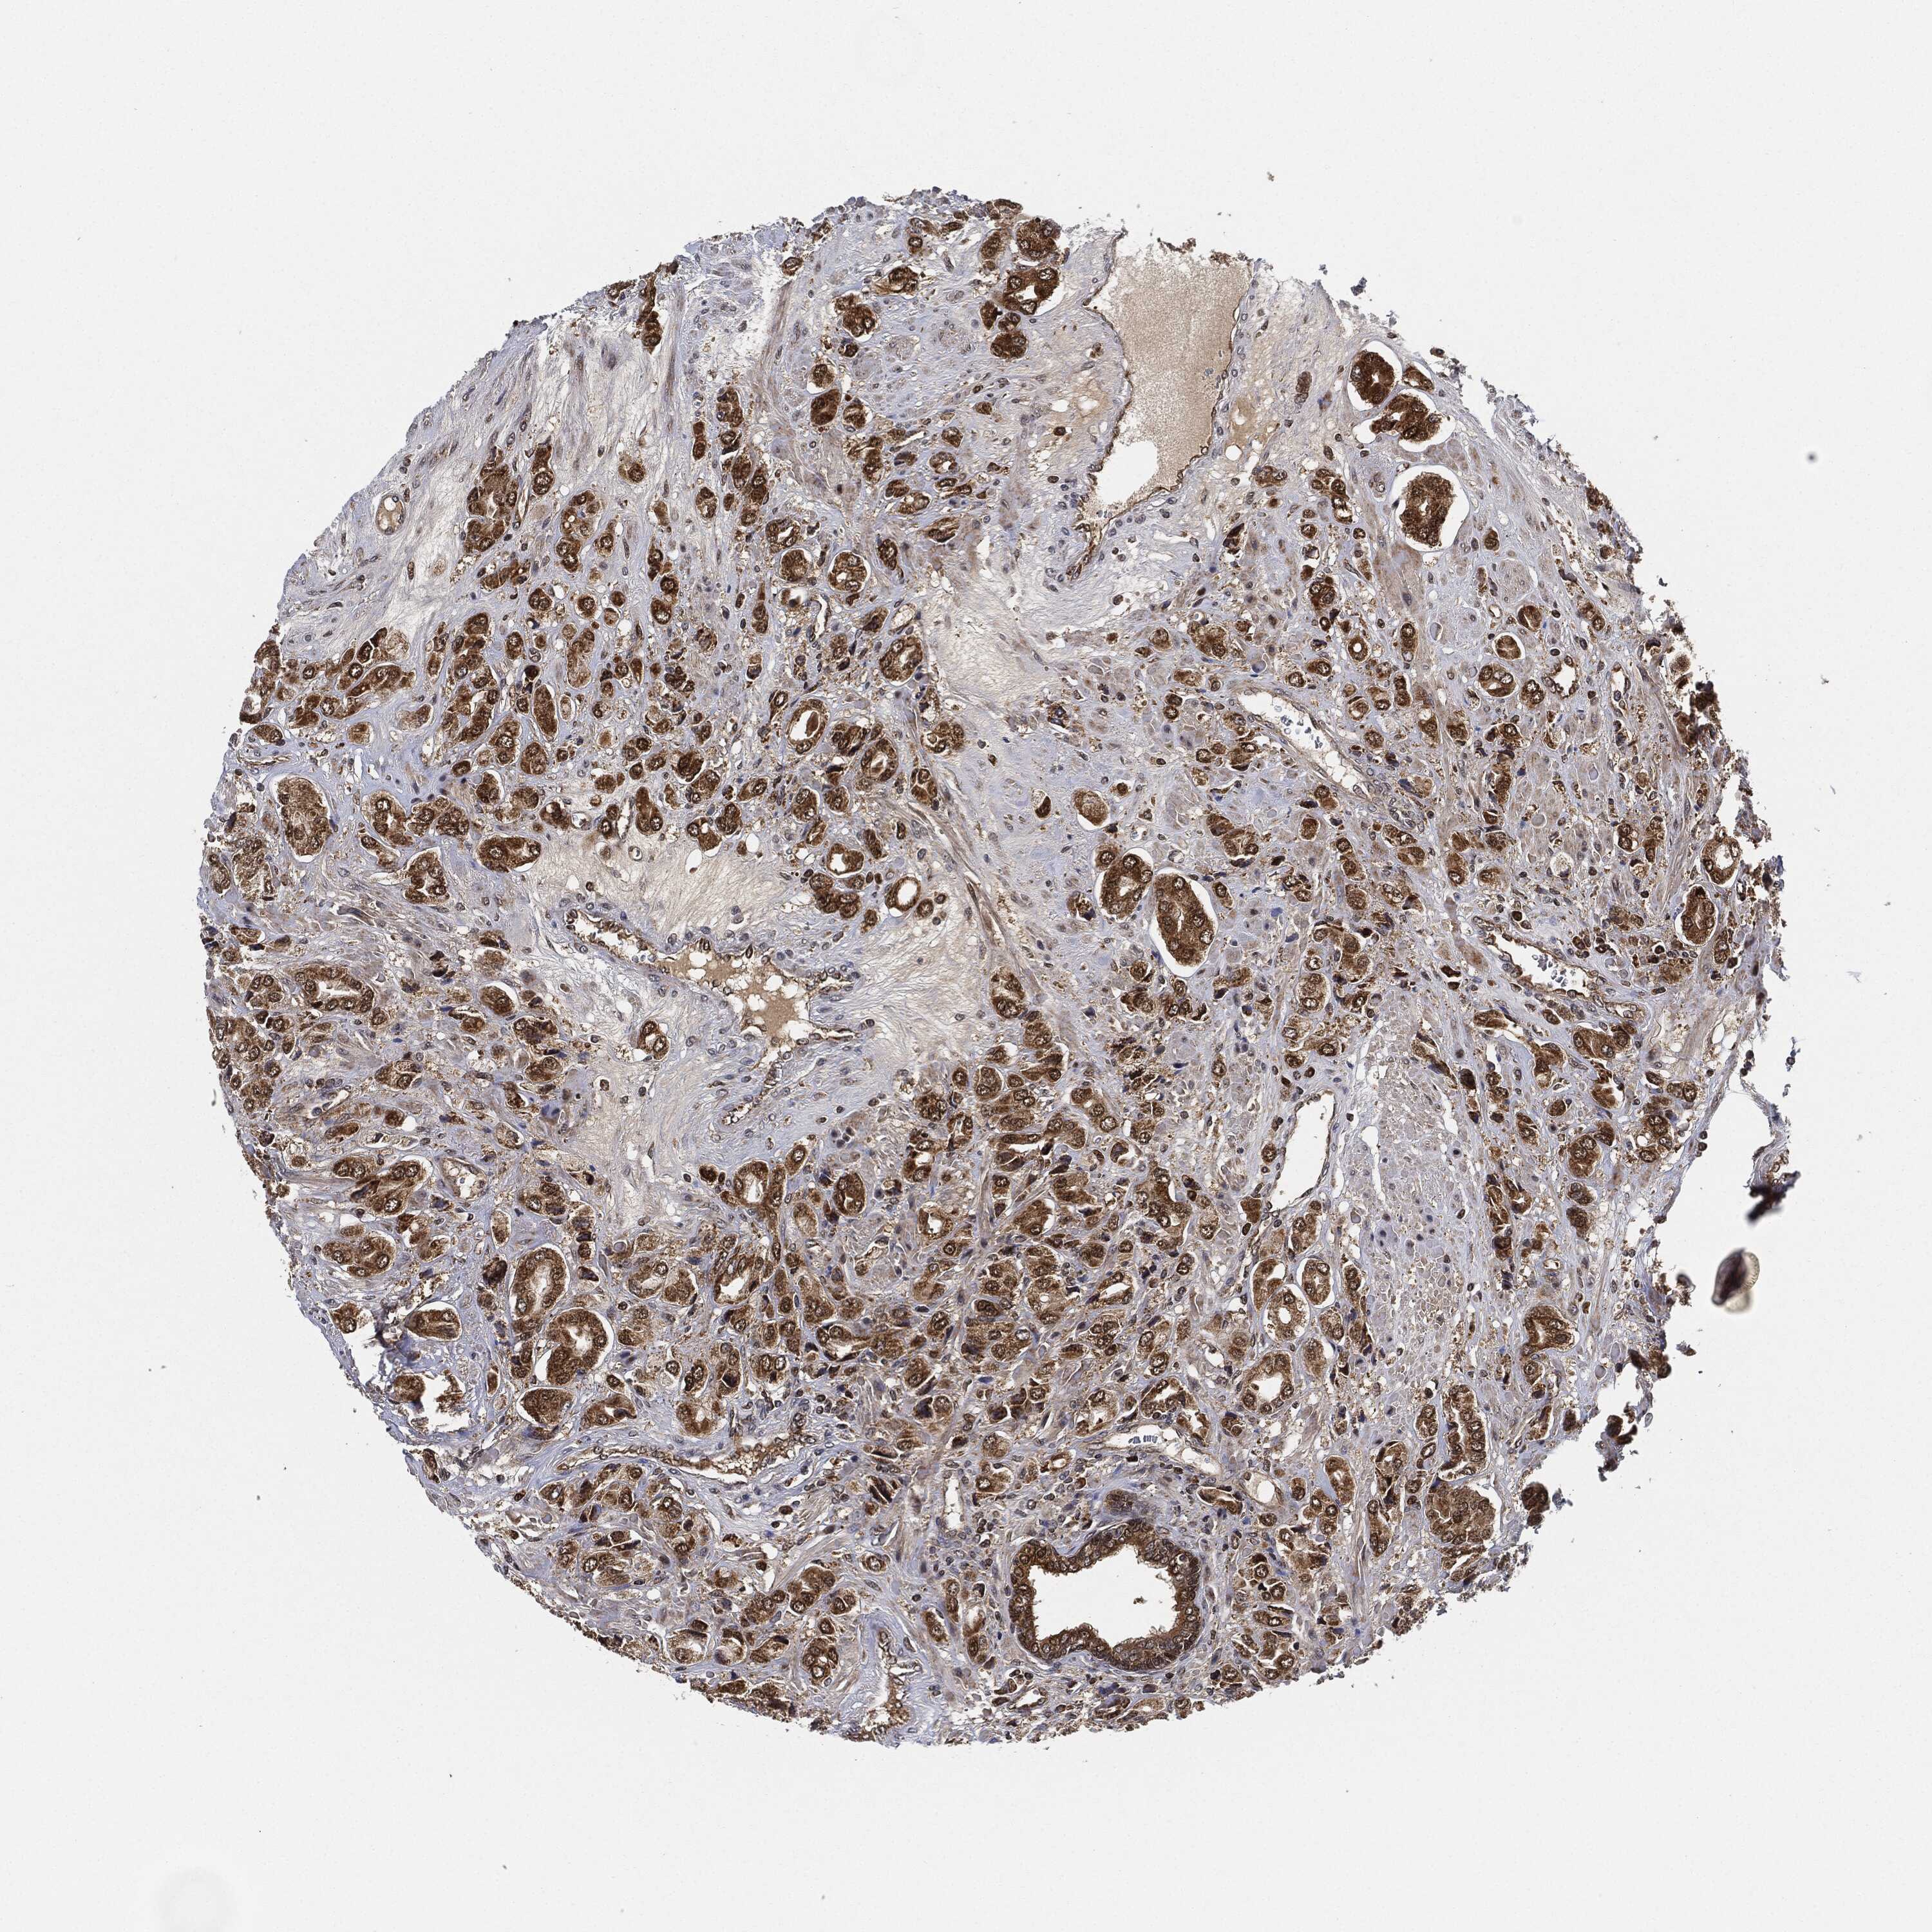

PROSTATE CANCER - Protein expressioni

A mouse-over function shows sample information and annotation data. Click on an image to view it in a full screen mode. Samples can be filtered based on level of antibody staining by selecting one or several of the following categories: high, medium, low and not detected. The assay and annotation is described here.

Antibody stainingi

Antibody staining in the annotated cell types in the current human tissue is reported as not detected, low, medium, or high, based on conventional immunohistochemistry profiling in selected tissues. This score is based on the combination of the staining intensity and fraction of stained cells.

Each image is clickable and will lead to virtual microscopy that enables deeper exploration of all samples and also displays staining intensity scores, fraction scores and subcellular localization as well as patient and tissue information for each sample.

Antibody HPA002633

Antibody HPA046758

Antibody CAB010906

Staining

High

Medium

Low

Not detected

Intensity

Strong

Moderate

Weak

Negative

Quantity

>75%

75%-25%

<25%

None

Location

Nuclear

Cytoplasmic/membranous

Cytoplasmic/membranous,nuclear

Adenocarcinoma, Medium grade

Adenocarcinoma, High grade

Adenocarcinoma, Low grade

Adenocarcinoma, NOS